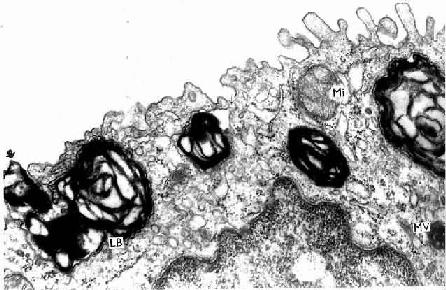

图14-14 人肺泡Ⅱ型细胞电镜像 ×42000

LB板层小体,Mi线粒体,MV多泡体,↑分泌